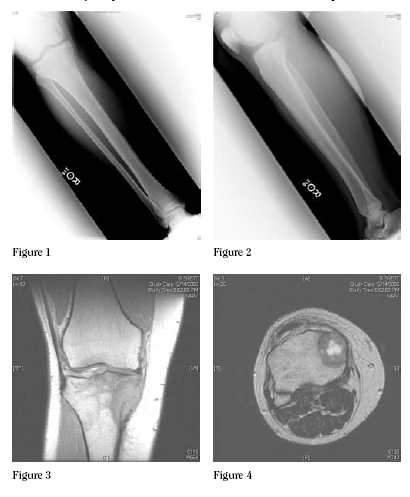

PrOxiMal T LeSiOn In A Y A : E D R - Home | OJHMS

Dian who suffered acute onset of right knee pain one Friday in December after a long day of work driving his pickup truck and clearing snow. The pain persisted over the weekend becoming severe enough on Sunday night that it woke him from sleep. ... Read More